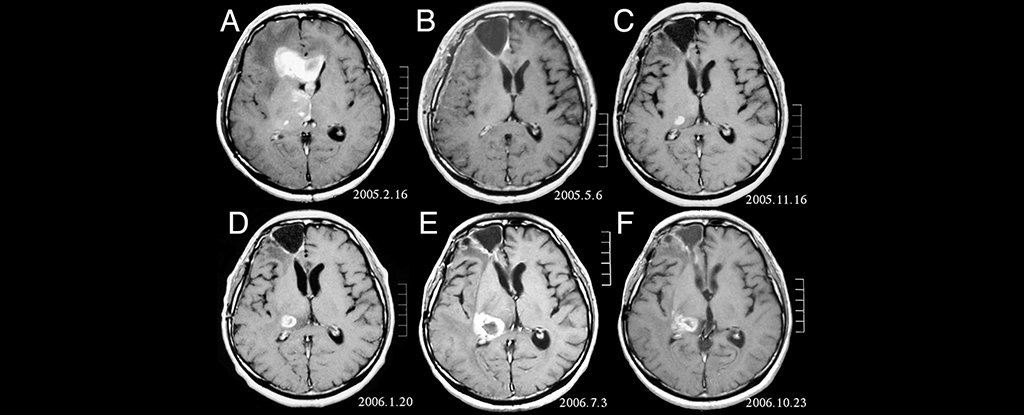

Essas células do cérebro podem levá-los a crescer fora de controle, fazendo com que se desenvolvam tumores cancerígenos. O glioma pode ser dividido em categorias, dependendo do tipo de célula glial em que começou.

Glioblastoma multiforme (GBM), por exemplo, é uma forma comum de câncer cerebral que começa como um tipo de célula glial chamada astrócito.

Tumores que crescem chegam a ser glioblastomas são particularmente agressivos, e matam cerca de 95% dos pacientes dentro de cinco anos. O GBM se desenvolve em cerca de 3 em cada 100.000 pessoas, principalmente naquelas com mais de 60 anos, e mata cerca 13.000 pessoas nos EUA e 5.000 no Reino Unido a cada ano.